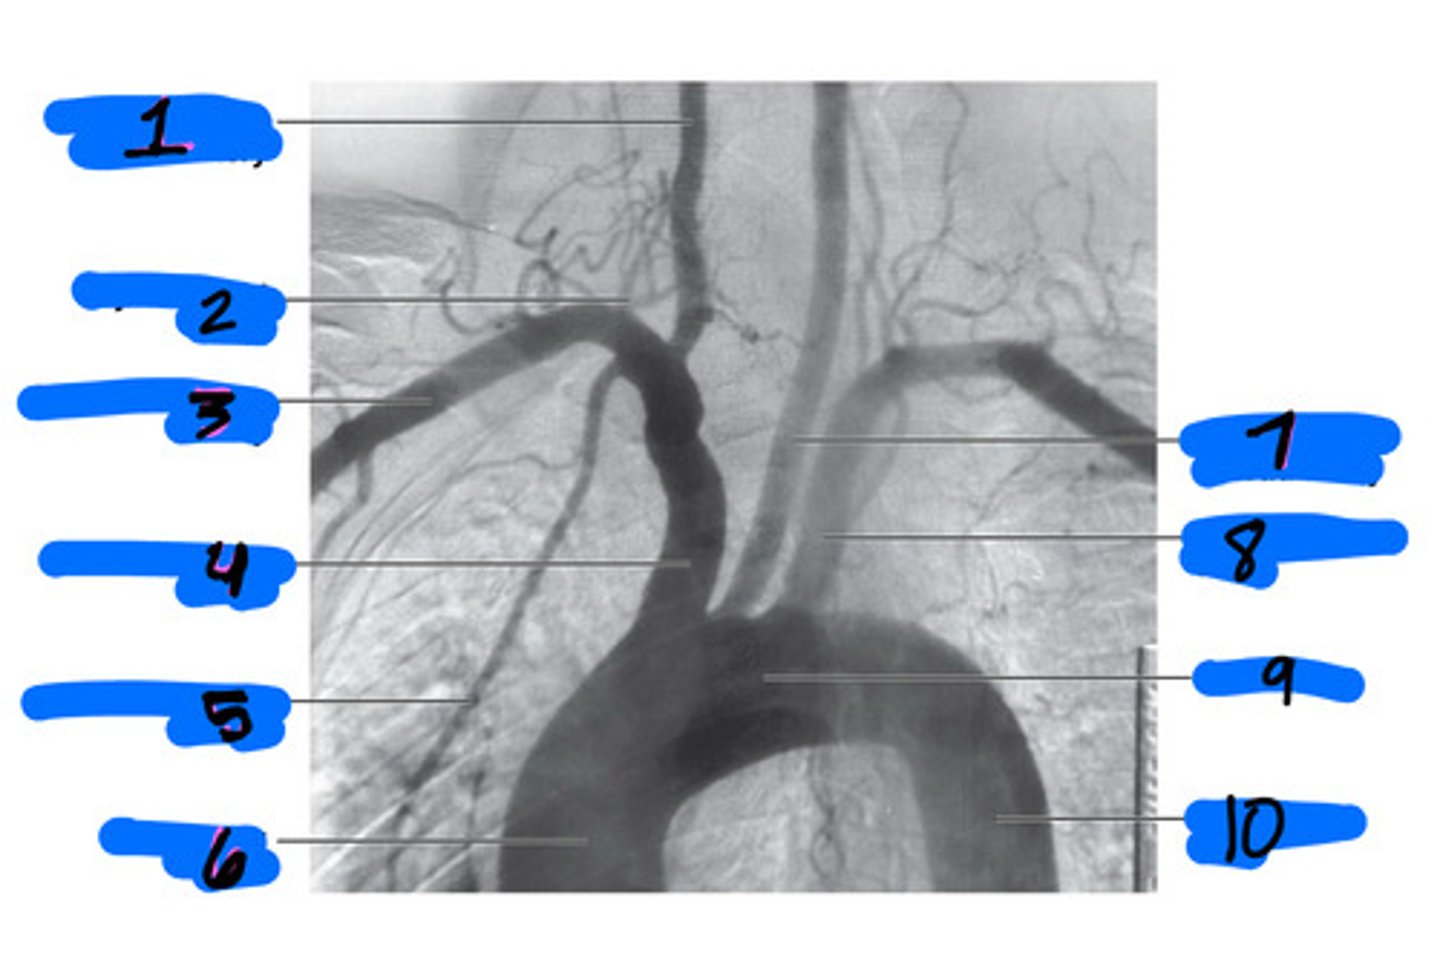

right common carotid artery

1

thyrocervical trunk

2

right subclavian artery

3

brachiocephalic trunk

4

internal thoracic artery

5

ascending aorta

6

left common carotid artery

7

left subclavian artery

8

aortic arch

9

descending aorta

10